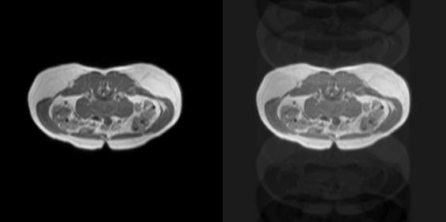

Liver MRI plays a crucial role in diagnosing various diseases; however, motion artifacts caused by patient movement during scanning can significantly degrade image quality, leading to misdiagnoses and additional scanning costs. This study explores a deep learning based retrospective motion correction (MoCo) approach using U-Net and Generative Adversarial Networks (GANs) to reduce motion artifacts in liver MRI images. Motion artifacts—including regular moving motion, ghosting effects, and spiking distortions—are simulated using TorchIO to generate training and validation datasets. The proposed model integrates Fully Convolutional Networks (FCNs), U-Net, and Patch-GAN to enhance feature learning through adversarial training. Additionally, perceptual loss is incorporated to test to improve the model’s ability to retain high-level details. The performance of the models is evaluated using the Structural Similarity Index (SSIM) to quantify image quality improvements. The study aims to demonstrate that deep learning-based MoCo can enhance liver MRI interpretation accuracy, reduce the need for repeated scans, and improve diagnosing efficiency while minimizing costs associated with motion artifacts.